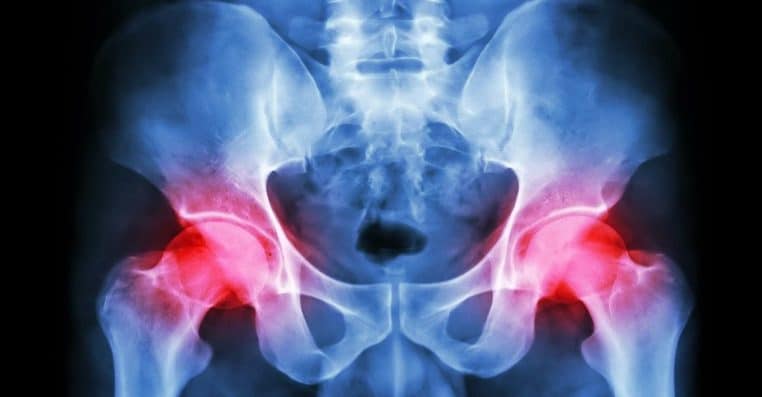

Il ajoute aussi : « Des recherches montrent également que si l’un de vos parents s’est cassé la hanche, vous êtes plus susceptible de vous fracturer un os. Les fractures de la hanche ont un taux de mortalité élevé et peuvent parfois entraîner une invalidité permanente ». Cela mérite de jeter un coup d’œil aux dossiers médicaux des membres de la famille !